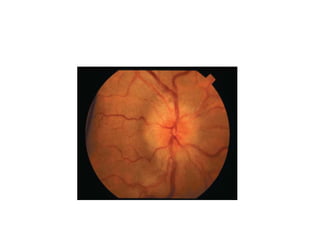

All patients should have a funduscopic

examination by an experienced clinician

looking carefully for

hemorrhages,exudates,and/or papilledema

All patients shouldhave a funduscopic examination by an experienced clinician looking carefully for hemorrhages,exudates,and/or papilledema